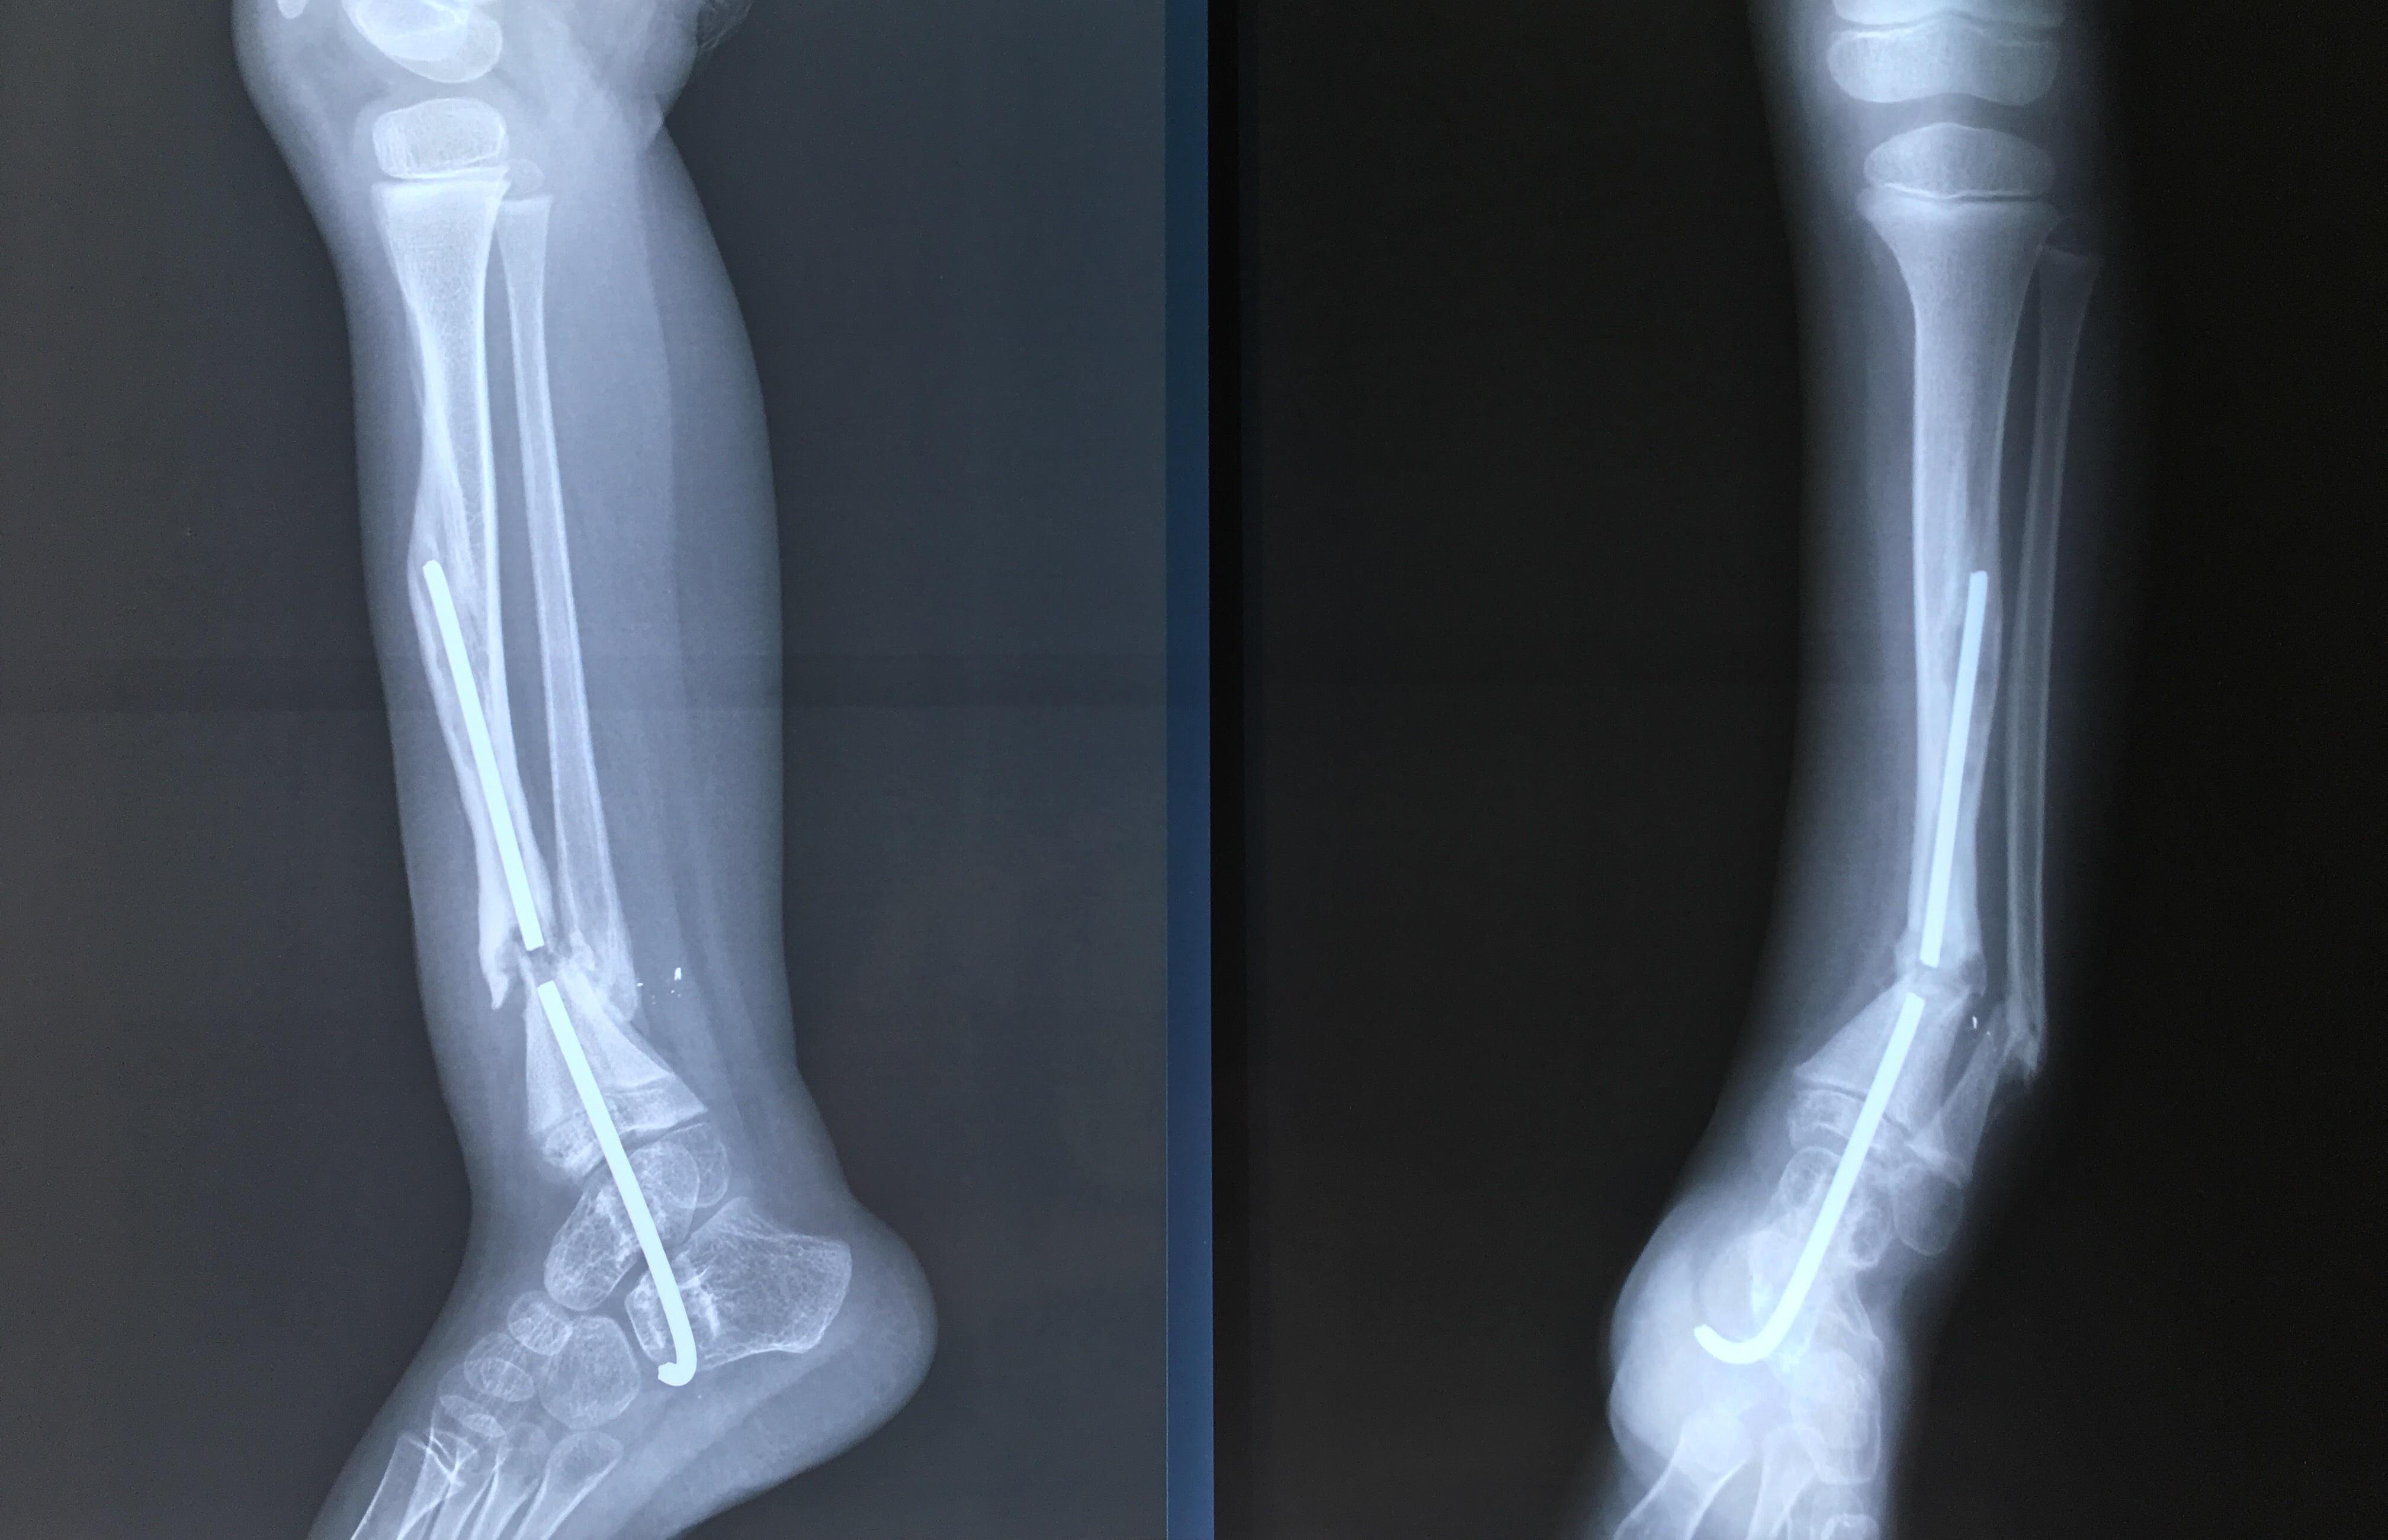

Phẫu thuật thành công ca bệnh hiếm gặp...khớp giả bẩm sinh xương chày

26/06/2019 17:00

Đã xem: 3441

Bệnh viện Chấn thương- Chỉnh hình Nghệ An, vừa phẫu thuật thành công cho bệnh nhi khớp giả bẩm sinh xương chày